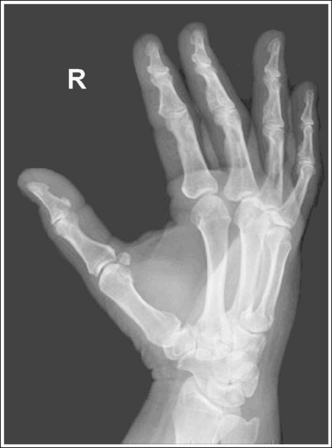

Hand: Posteroanterior Oblique Projection (External Rotation)

See Figure 4-24 and Box 4-9.

The hand has been externally rotated 45 degrees. Each of the second through fifth metacarpal midshafts demonstrate more concavity on one side than on the other and have varying amounts of space between them. The first and second metacarpal heads are not superimposed, the third through fifth metacarpal heads are slightly superimposed, and a slight space is present between the fourth and fifth metacarpal midshafts.

• To accomplish a PA oblique hand projection, begin with the hand in a PA projection. Then, externally rotate the hand until it forms a 45-degree angle with the IR (Figure 4-25). To confirm the 45-degree angle, it is best to view the hand and not the wrist. The wrist will demonstrate more than 45 degrees of obliquity when the hand is in a 45-degree oblique projection, so using the wrist can result in a miscalculation of the amount of obliquity. This is especially true if the humerus and forearm have not been placed on the same horizontal plane. When the patient has been positioned with the arm on the same horizontal plane, the ulnar styloid is demonstrated in profile medially on the image. A radiolucent immobilization device can be used to help maintain this position.

• Verifying PA oblique hand projection. A 45-degree PA oblique hand projection can be recognized by the amount of metacarpal midshaft and metacarpal head superimposition. If the hand has not been rotated enough, the metacarpal relationship is similar to that demonstrated on a PA projection of the hand: The midshafts of the metacarpals are almost evenly spaced, and the metacarpal heads are not superimposed (see Image 22). On a 45-degree PA oblique hand projection, a space should be maintained between the fourth and fifth metacarpal midshafts. If the hand is rotated more than 45 degrees, this space is obscured and the fourth and fifth metacarpals demonstrate some degree of superimposition (see Image 23).

Image 22

Image 23

No soft tissue overlap of adjacent digits is present.

• Fingers should be spread slightly to prevent soft tissue overlapping (Images 24 and 25).

The IP and MP joints are visible as open spaces, and the phalanges are demonstrated without foreshortening. The thumb's position may vary from a lateral to a PA oblique projection.

• The IP and MP joint spaces are open and the phalanges are not foreshortened when the hand and fingers are fully extended and aligned parallel with the IR. An immobilization device should be used to help the patient maintain this positioning.

• Disadvantages of using fingers as prop. A common positioning error in PA oblique hand projection is to use the patient's fingers instead of an immobilization device to maintain the oblique position. For this positioning, the fingers are flexed until the fingertips touch the IR to prop the hand (Figure 4-26). Such positioning closes the IP joint spaces and foreshortens the phalanges (Images 23 and 25).

The third MP joint is at the center of the exposure field. The distal, middle, and proximal phalanges, the metacarpals, the carpals, and approximately 1 inch (2.5 cm) of the distal radius and ulna are included within the collimated field.

• Center a perpendicular central ray to the third MP joint to place it in the center of the collimated light field. The MP joint is situated just slightly distal to the head of the third metacarpal. Once the central ray is centered, open the longitudinal collimation to include the distal phalanges and the distal forearm. Transversely collimate to within 0.5 inch (1.25 cm) of the first and fifth finger's skin line.

• Either half of a 10- × 12-inch (24- × 30-cm) detailed screen-film IR placed crosswise or a single 8- ×10-inch (18- × 24-cm) digital IR placed lengthwise should be adequate to include all the required anatomic structures.

The metacarpal heads demonstrate only slight superimposition, the metacarpal midshaft concavities are fairly uniform, and the spaces between the metacarpal midshafts are almost equal. The hand was not rotated enough. Open collimation includes 1 inch of radius and ulna.

The midshafts of the third through fifth metacarpals are superimposed. The patient's hand was placed at more than 45 degrees of obliquity. The phalanges are foreshortened, and the IP joints spaces are closed. The fingers were not positioned parallel with the IR, but instead were used to prop the hand (see Figure 4-26).

Internally rotate the hand until the metacarpals and the IR form a 45-degree angle and extend the fingers, placing them parallel with the IR.

Soft tissue and bony structure overlap of the digits is present. The fingers were not spread apart.

The distal and middle phalanges are foreshortened, and the IP joint spaces are closed. The fingers were not positioned parallel with the IR, but were instead used to prop the hand (see Figure 4-26).